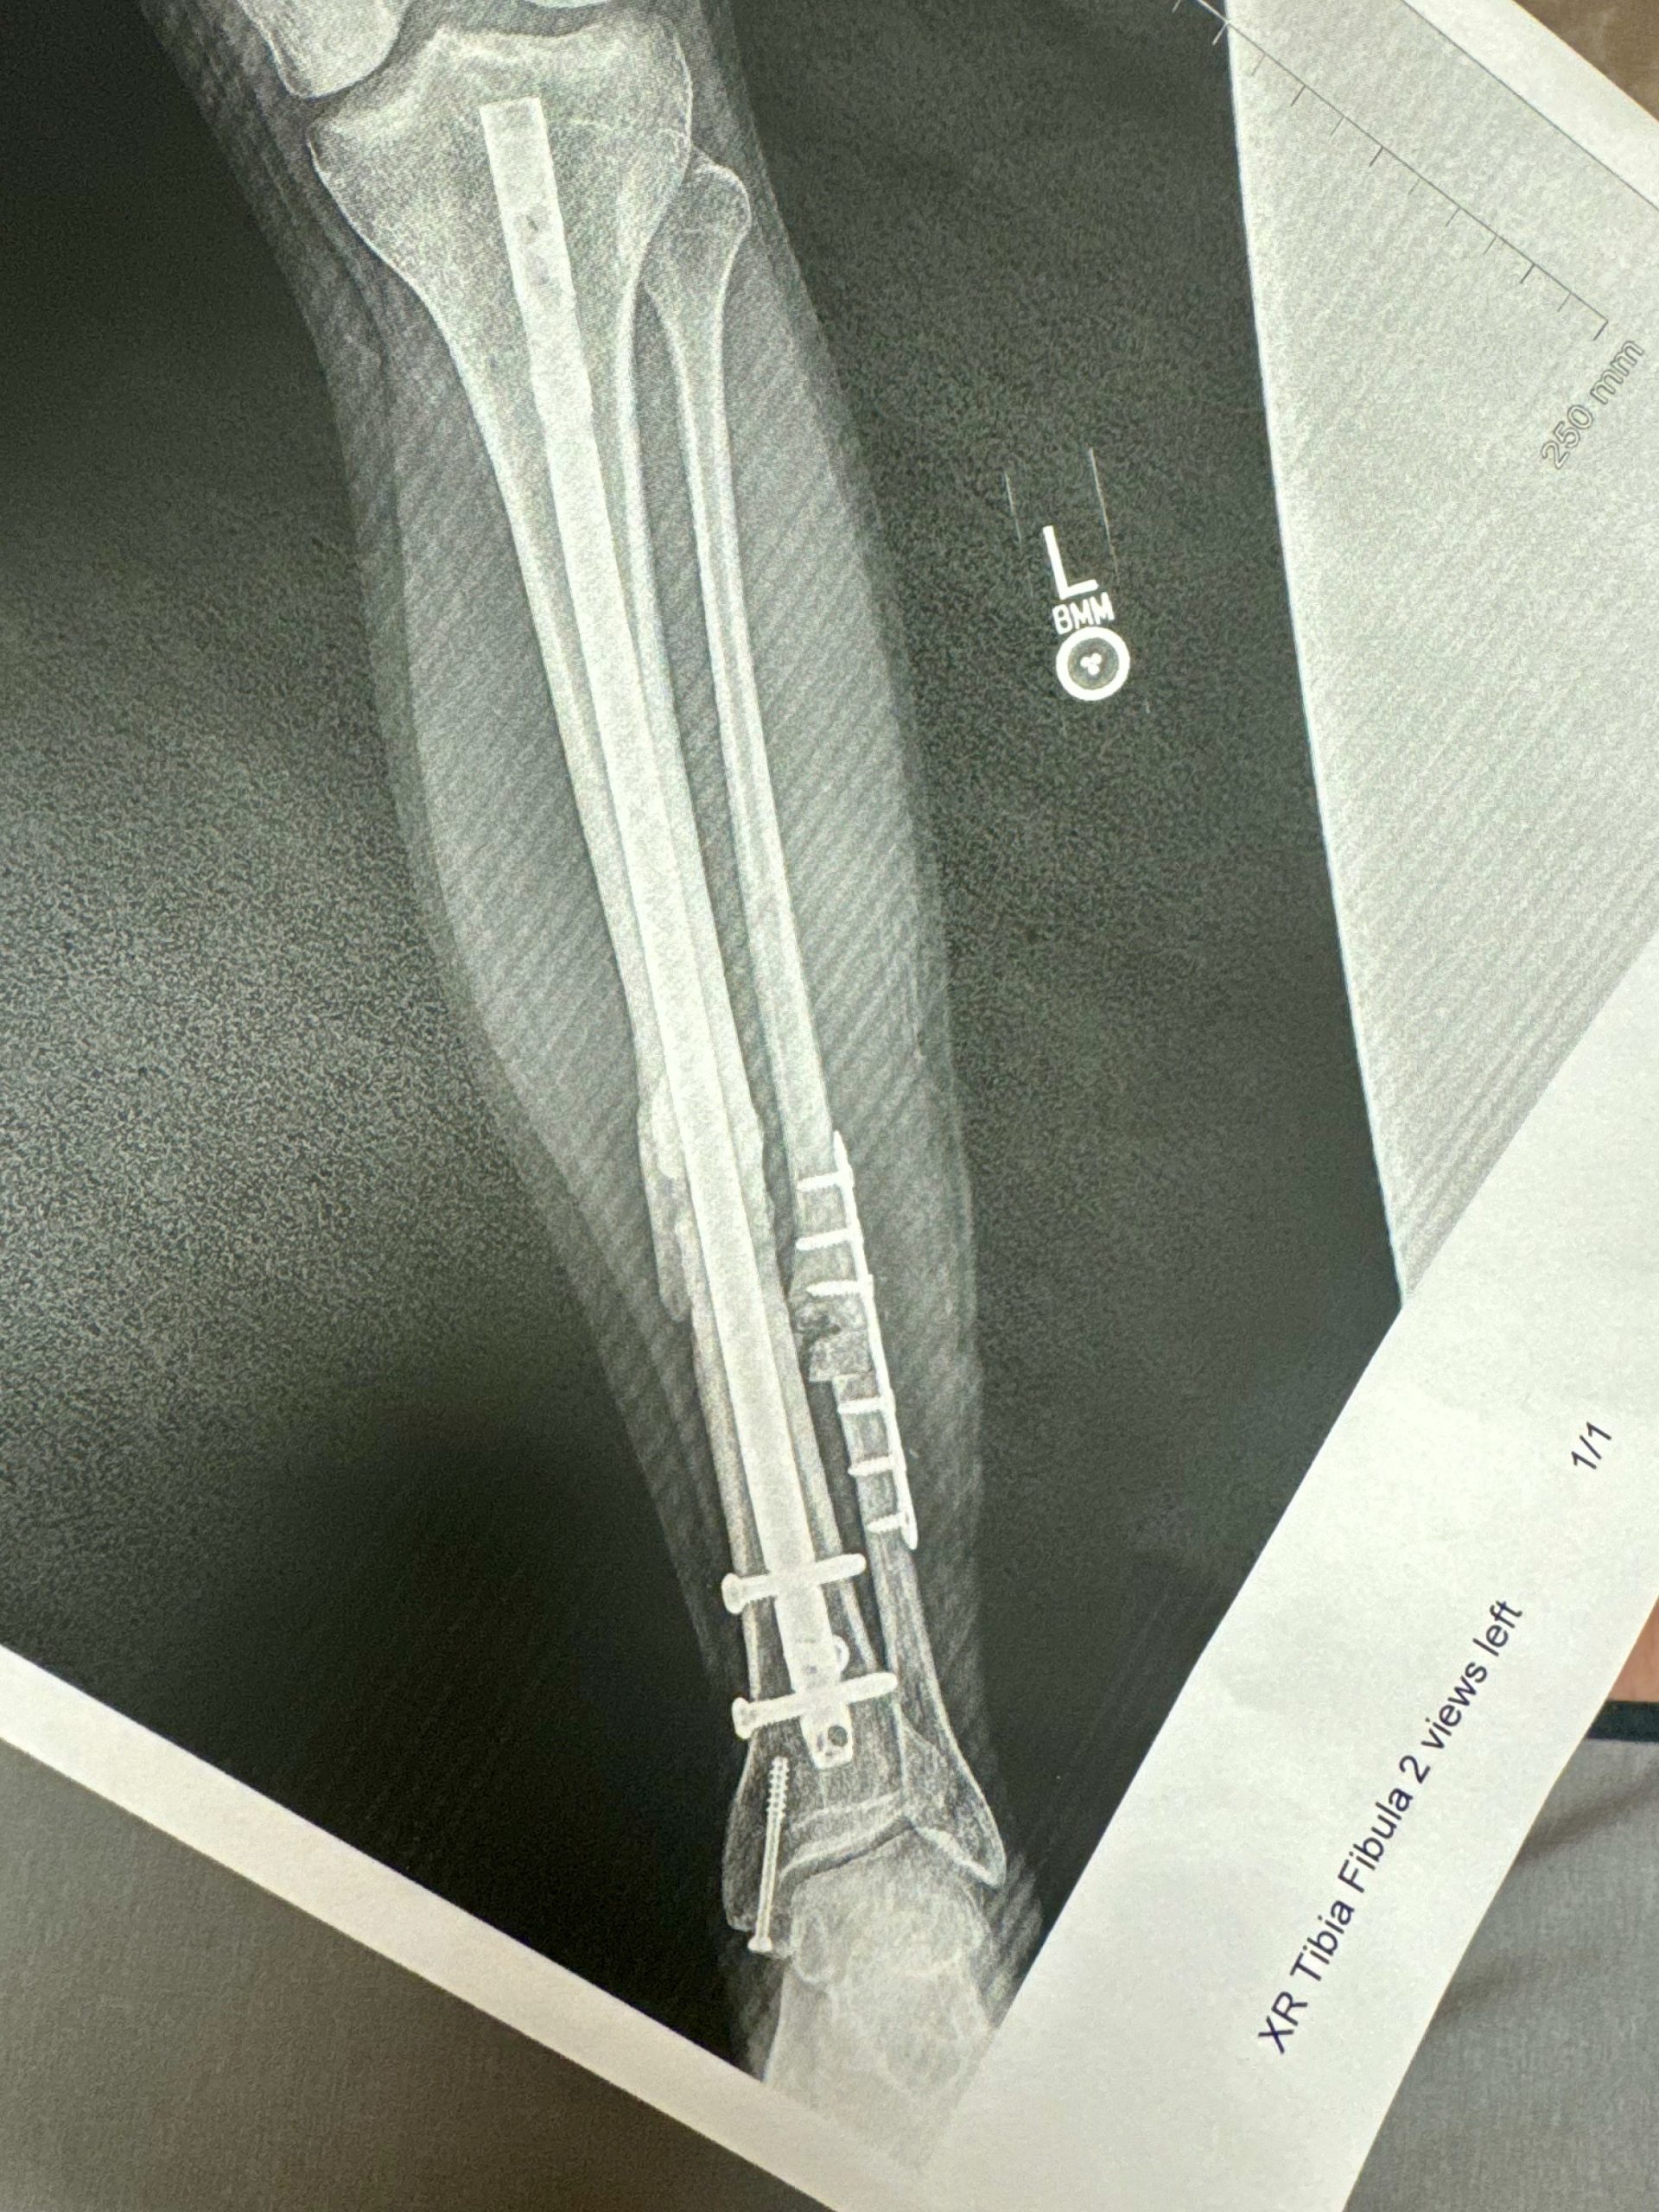

He suffered compound fractures of his left tibia and fibula that not only ended his 2023 season, but it is now jeopardizing his 2024 season, as well. With the MotoAmerica Championship looming large, Ventura had to make the difficult decision to have additional surgery due to continued complications from the injuries.